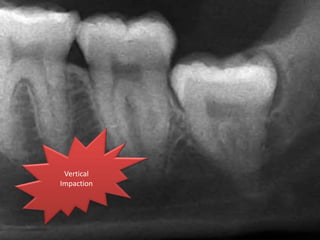

Angulation of impaction

Based on Winter's classification, the angle between the

longitudinal axis of the second and third molars

Vertical

impaction